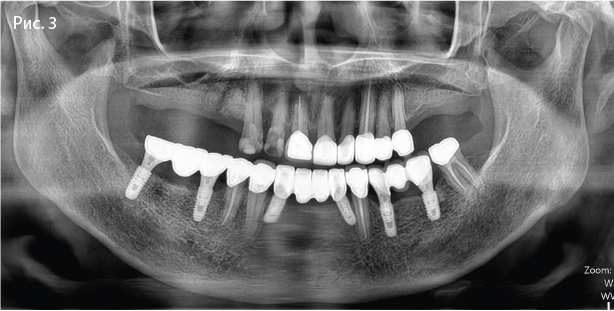

Контрольная панорамная рентгенограмма

Имплантаты в позиции 45, 47 (Osstem TSIII SOI 45: 4,0x10,0; 47: 5,0x10,0)

Имплантаты в позиции 34, 36 (Osstem TSIII SA 34: 4,0x10,0; 36: 5,0x8,5)